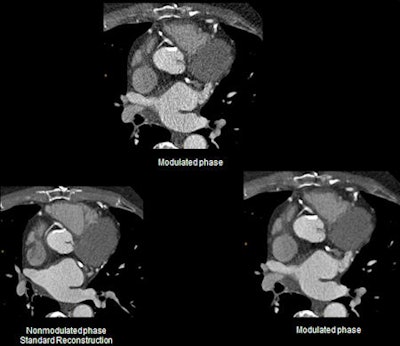

"It is important to note that a simple change to a previous full-dose protocol fitting for all anatomic regions and examination types is not reasonable. For example, with CT angiographies we see the potential for dose reductions of more than 50% with the use of higher iDose levels," Fingerle pointed out.

Standard FBP reconstruction is unable to guarantee diagnostic image quality when lowering radiation dose in CT due to an inherent increase in image noise, and iterative reconstruction algorithms have been developed as an alternative to FBP. Reconstruction based on these algorithms used advanced mathematical models to decrease image noise and remove artifacts with lower tube currents, concluded Fingerle.

Sophisticated image reconstruction algorithms have been developed over the past few years. A key factor has been the significant increase in computing power necessary for image reconstruction algorithms beyond standard filtered back projection (FBP). At the TUM, radiologists have worked on the clinical integration of iDose from Philips Healthcare on a 256-slice multidetector CT unit (Brilliance iCT) to lower radiation dose while retaining an image quality at least equal to standard FBP reconstruction. They presented their findings at the recent RSNA congress.